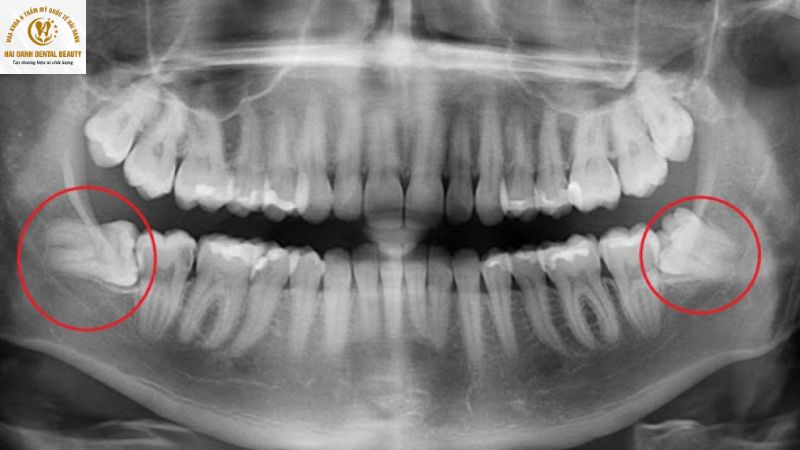

- Mọc nghiêng: Răng khôn mọc lệch và đâm thẳng vào răng số 7 (răng hàm lớn thứ hai) ngay bên cạnh. Tình trạng này có thể gây tổn thương, sâu răng hoặc xô lệch các răng khác.

- Mọc ngầm: Răng khôn nằm hoàn toàn dưới nướu và xương hàm, không thể nhú lên được. Răng ngầm có thể gây đau âm ỉ, u nang và ảnh hưởng nghiêm trọng đến xương hàm.

- Răng khôn mọc lệch, mọc ngầm: Đây là tình trạng phổ biến nhất, khi răng khôn mọc nghiêng, đâm vào răng số 7 bên cạnh hoặc kẹt dưới xương hàm. Tình trạng này gây ra đau nhức dai dẳng, viêm nhiễm tái phát và có thể làm xô lệch các răng khác.

Răng khôn mặc lệch ảnh hưởng đến răng số 7 ăn nhai chính nên nhổ để bảo vệ răng.